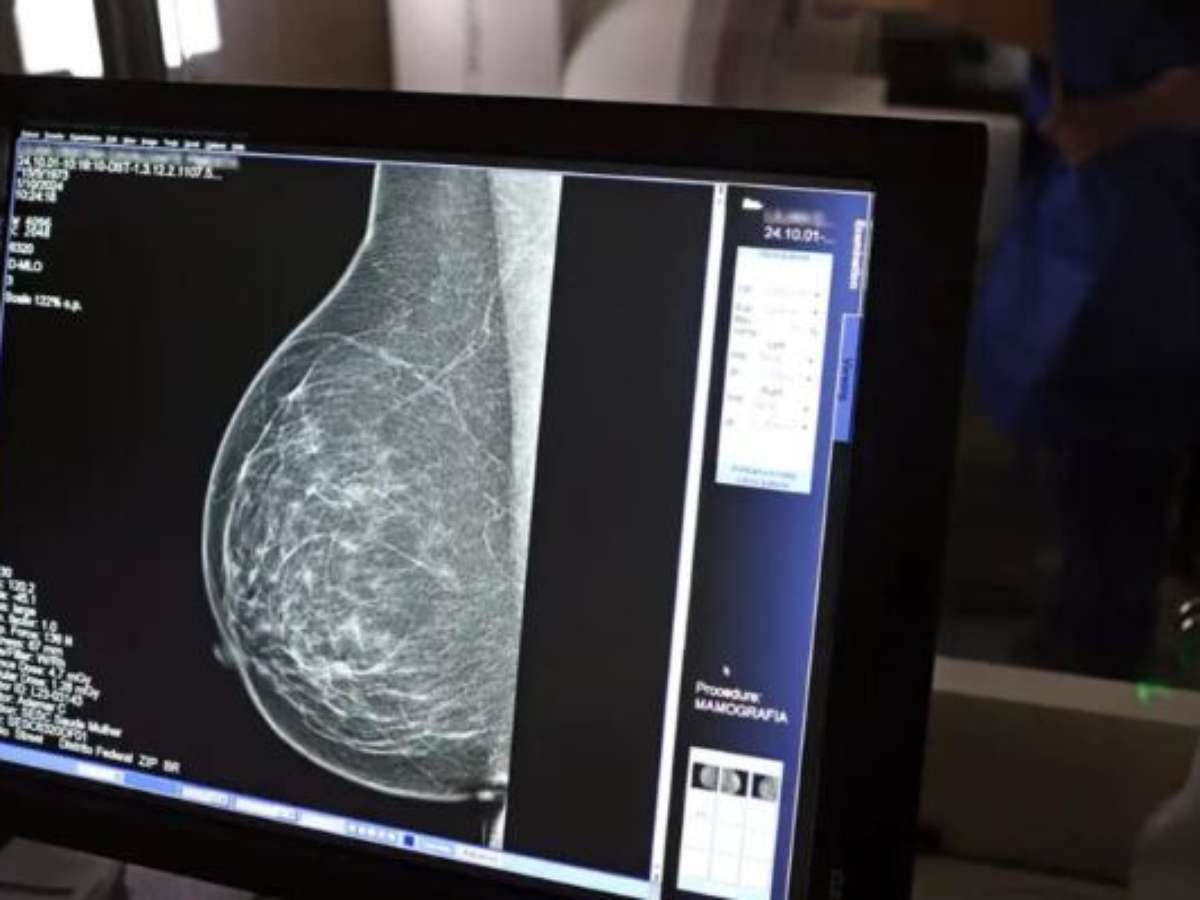

Foto: José Cruz/Agencia Brasil / Porto Alegre 24 horas

A média atual de oferta é de 4 mil vagas mensais, distribuídas entre hospitais e clínicas credenciadas. Em 2024, a média de mamografias mensais era de 2,6 mil. Desde março, com a aquisição de um mamógrafo de última geração e a abertura de 900 agendas mensais no Hospital Vila Nova, a secretaria conseguiu acelerar o ritmo de atendimentos e dar uma resposta efetiva à população.